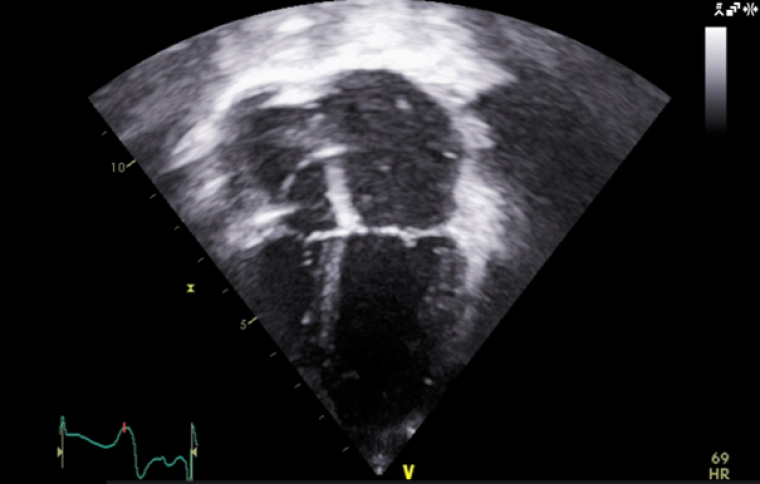

At the age of 4 years, the patient started developing a distinct echocardiographic phenotype (Image 5), with a dilated left atrium (LA) (LA area 12.1 cm3, z score +5.7) and right atrium (RA) (RA area 10.8 cm3, z score +4.1), preserved global left ventricular systolic function, but impaired longitudinal function (tissue doppler lateral S’ wave 0.07m/s, septal 0.05m/s) and evidence of early impaired left ventricular relaxation (isovolumetric relaxation time 114ms, pulmonary vein A-wave duration 166msm abnormal mitral valve doppler). The left ventricle itself was normal in size, with a maximal wall thickness of 5-6mm (z score +02), with no significant valvular or other abnormalities.